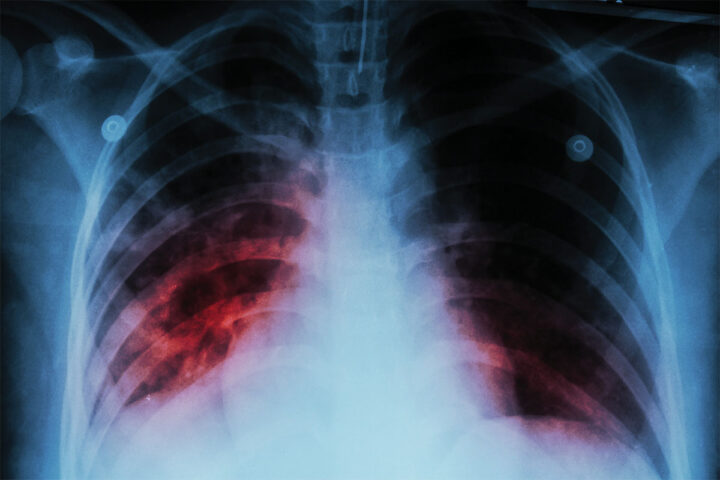

Infecção letal

A Organização Mundial da Saúde (OMS) divulgou um relatório global em novembro reforçando que a tuberculose, uma das doenças infecciosas mais mortais do planeta, continua fazendo milhares de vítimas. Em 2024, foram registrados 10,7 milhões de novos casos e mais de 1,2 milhão de mortes. A OMS aponta que 87% das infecções ocorreram em 30 países, sendo que oito deles são responsáveis por 66,9% do total: Índia (25%), Indonésia (10%), Filipinas (6,8%), China (6,5%), Paquistão (6,3%), Nigéria (4,8%), República Democrática do Congo (3,9%) e Bangladesh (3,6%). O Brasil não figura entre os de maior incidência da doença, mas registrou 84.308 casos em 2024.

De acordo com o Ministério da Saúde, a enfermidade, transmitida pelo ar, espalha-se facilmente em locais com aglomeração e afeta principalmente os pulmões, embora outros órgãos, como rins e sistema nervoso, também possam ser comprometidos. Cientistas pontuam que, além dos sintomas mais frequentes – tosse com secreção, cansaço intenso e perda acentuada de peso –, nos casos mais graves há risco de destruição do tecido pulmonar e insuficiência respiratória. Entre os fatores que favorecem a disseminação da doença, destacam-se: desnutrição, HIV, diabetes, tabagismo, consumo de álcool e questões estruturais, como pobreza e dificuldade de acesso a serviços de saúde. (Patrícia Scott com informações de UOL Saúde)